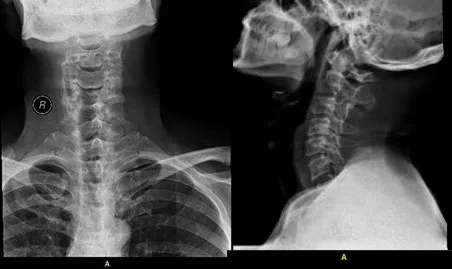

术前影像资料